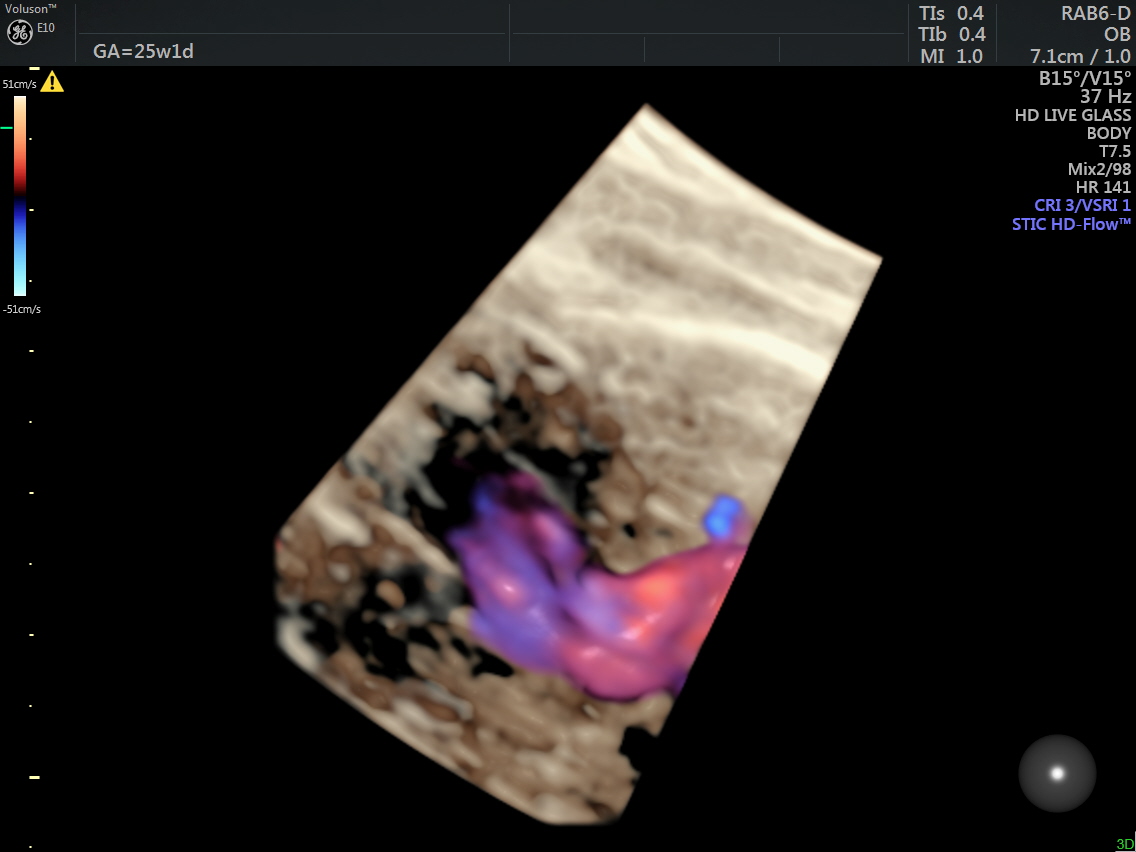

This was a 25-year-old primi referred for a 2nd opinion for Double Outlet Right Ventricle. No VSD was detected by the sonologist.

The following are some reconstructions.

This fetus showed left heart dysplasia, a small VSD and Double Outlet Right Ventricle with malposition of the great arteries.